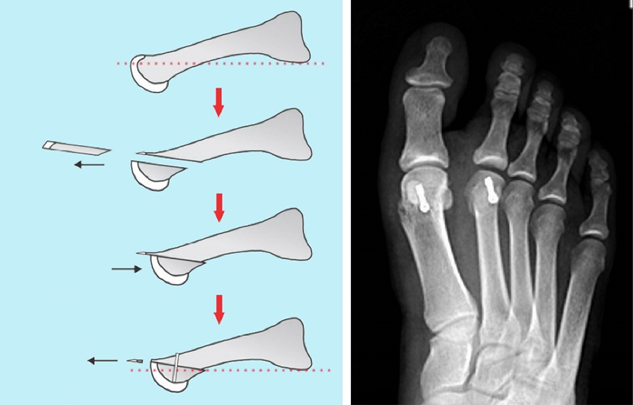

左图为跖痛症矫形手术示意图,通过截骨将跖骨短缩同时抬高跖骨头,红色虚线为水平线,矫形后跖骨头抬高约3mm。右图示跖骨截骨内固定术后X光片。